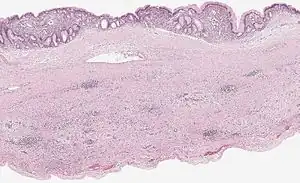

Mucinous cystadenoma of the pancreas